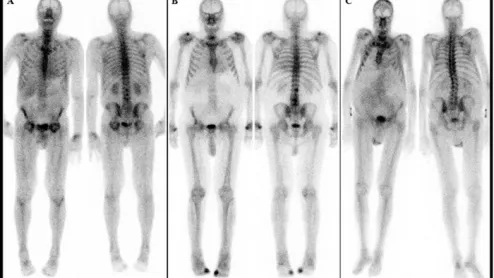

cardiac amyloidosis on bone scan